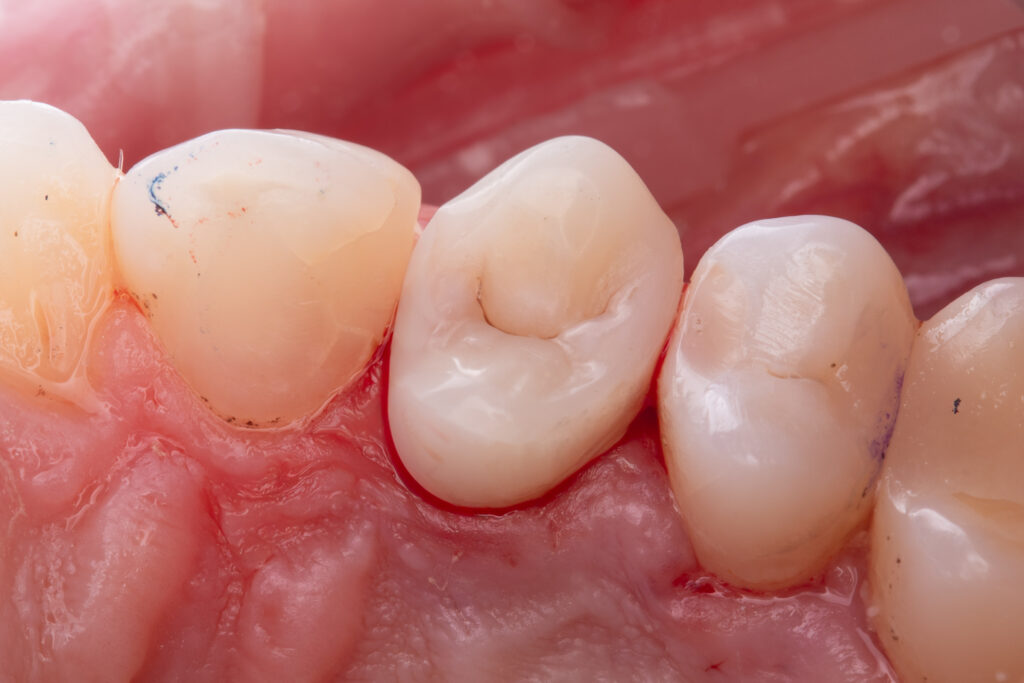

The second visit was dedicated to replacement of the old restoration and placement of a fiberglass post (EverX Dentin Shade was used), followed by restoration with Asteria A1B+, NeoSpectrum A2, and Enamel Brown stain.

The total time for restoration replacement was 1 hour and 30 minutes.